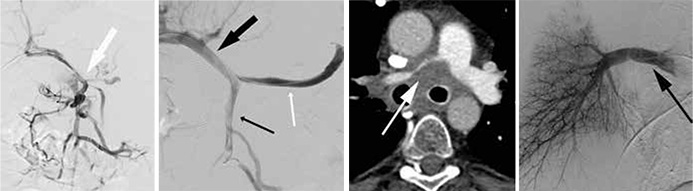

Översikt Nu introduceras nya metoder vid såväl maligna som benigna sjukdomar